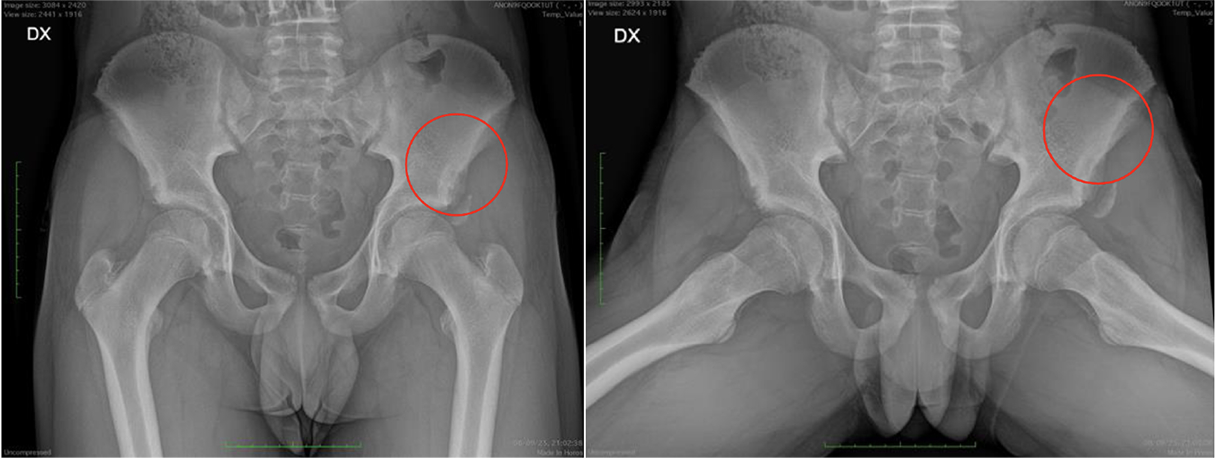

1-Beat Cardiac migliora la qualità diagnostica dell’angio-TC coronarica

L’angio-TC coronarica (CCTA) è uno strumento diagnostico essenziale per l’identificazione delle malattie coronariche, ma la sua affidabilità può essere compromessa nei pazienti con frequenza cardiaca elevata. Grazie ai progressi tecnologici, la modalità 1-Beat Cardiac consente ora di ottenere immagini di alta qualità anche in condizioni di elevata frequenza cardiaca.